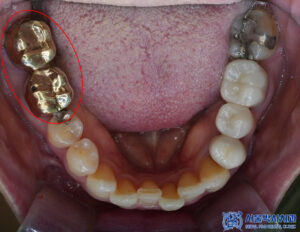

확인해 보니,

오래전 치료를 받은

브릿지 보철들이 관찰되었는데요.

보철이 마모가 되고 깨져

안에 금속이 드러나 있는

부분이 보였습니다.